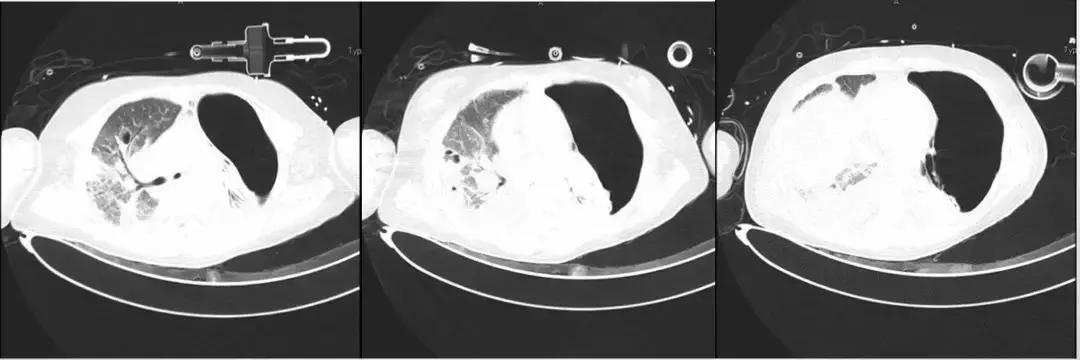

7月10日:

*影像学仍持续变化:

左侧胸腔病变为肺大泡?气胸?如何处理?药物是否需要调整?